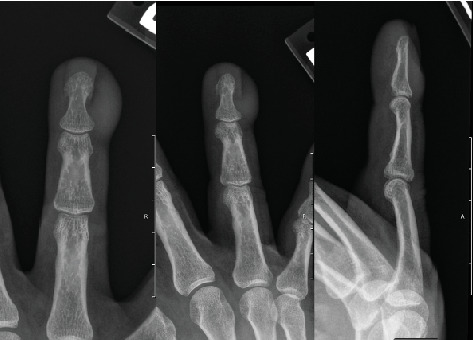

摘要指乳头状腺癌是一种罕见的恶性肿瘤,常被误诊为良性。一名57岁的白人男性,复发性甲沟炎,右四趾远端指骨皮下肿块,在发病5年后寻求手部手术评估后被诊断为DPA。边缘切除活检呈金黄色葡萄球菌感染和DPA阳性,导致手术切除并经中指骨截肢。DPA虽然罕见,但通常表现不明显,导致诊断延迟和转移风险增加。这种肿瘤有很高的复发和转移率,最常见于肺和淋巴部位。由于DPA与多种良性皮肤疾病相似,因此准确诊断DPA具有挑战性。目前的治疗重点是手术切除,重点是阴性切缘。前哨淋巴结活检没有常规进行,尽管由于DPA的罕见性很难建立指南。诊断和治疗DPA可以减少转移和复发。出现顽固性或复发性皮肤病变的患者应考虑DPA。手术管理仍然是主要的治疗策略,需要持续的研究来优化治疗方案和后续护理。

Digital papillary adenocarcinoma (DPA) is a rare malignant eccrine tumor often misdiagnosed as a benign condition. A 57-year-old Caucasian male with recurrent paronychia and a subcutaneous mass on the distal phalanx of the right fourth digit was diagnosed with DPA after seeking hand surgery evaluation 5 years following onset. A marginal excisional biopsy was positive for Staphylococcus aureus infection and DPA, leading to surgical excision with transmiddle phalangeal amputation for negative margins. DPA, while rare, often presents insidiously, leading to delayed diagnosis and increased risk of metastasis. This tumor has high rates of recurrence and metastasis, most commonly to pulmonary and lymphatic sites. Accurate diagnosis of DPA is challenging due to its resemblance to multiple benign cutaneous conditions. Current treatments focus on surgical excision, with an emphasis on negative margins. Sentinel lymph node biopsy is not routinely performed, although guidelines are difficult to establish due to the rarity of DPA. Diagnosing and treating DPA minimizes metastasis and recurrence. DPA should be considered in patients presenting with recalcitrant or recurring cutaneous lesions. Surgical management remains the primary treatment strategy, with ongoing research needed to optimize treatment protocols and follow-up care.